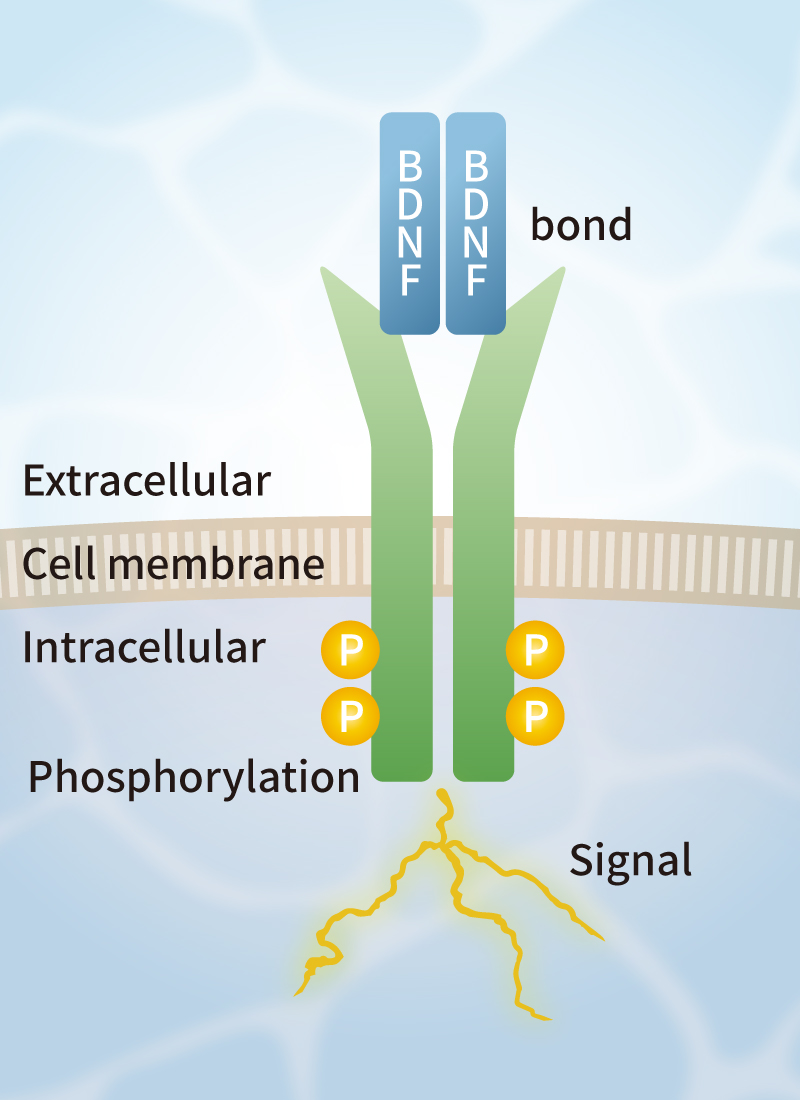

Solve challenges of conventional growth factors

Challenges of conventional growth factors

Currently, FBS and recombinant growth factors are used for cell culture. However, such products have some challenges such as variation in quality among production lots, contamination by biological impurities, low stability, and extremely high prices.